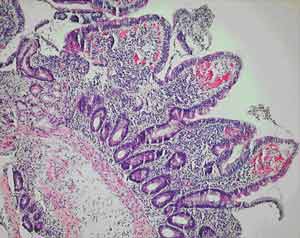

The clinical presentation, histological findings and response to tetracycline and folate therapy in our patients, seen at Cairns Base Hospital between 1998 and 2004, support a diagnosis of tropical sprue. To our knowledge, these are the first reported cases in Australia.

All of our patients were Indigenous patients living in remote Indigenous communities. The alcohol use by the first patient clouds the picture, as high alcohol intake is associated with nutritional deficiencies. However, the partial villous atrophy on biopsy is more suggestive of tropical sprue. Additionally, despite being in hospital and not drinking alcohol for 2 weeks, there was no response in his weight or biochemical test results until therapy for tropical sprue commenced. Finally, his weight gain and improvement in biochemical test parameters continued despite ongoing alcohol misuse on discharge.

The absence of an agreed definition for tropical sprue has created difficulties. It has been noted that many asymptomatic people living in the tropics will have subclinical malabsorption and even abnormal small bowel biopsy results when rigorously assessed. Uncertainty in the diagnosis of tropical sprue is compounded by the condition’s incompletely understood aetiology. It is proposed that gastrointestinal infections, which occur at a higher rate in the tropics, cause mucosal injury and initiate the process. The mucosal injury leads to a disturbance in intestinal motility, allowing the overgrowth of coliform bacteria in the small bowel.1,2 Enterotoxins from these bacteria potentiate the mucosal damage which leads to malabsorption and protein loss. The resulting nutritional deficiencies hinder epithelial recovery, and a vicious circle develops. Alteration in the intestinal microflora may also lead to a change in toll-like receptor signalling and further retardation of intestinal healing.3

A number of studies of chronic diarrhoea in Indigenous Australian children have documented partial villous atrophy on small bowel biopsy.6,7 Higher colony counts and more frequent isolation of gram-negative organisms are found in duodenal aspirates from Indigenous children with chronic diarrhoea.8 Some of these studies noted a similarity with contemporary Indian studies of tropical sprue, but therapy with antibiotics and folate does not seem to have been considered in the Indigenous children.

Our anatomical pathology service believes that small-bowel biopsies from Indigenous patients from remote communities do show a subtle increase in inflammatory cells (Dr M Jagusch, Anatomical Pathology Department, Cairns Base Hospital, personal communication), perhaps representing the subclinical tropical enteropathy described above. The relatively high incidence of gastrointestinal infections in these Indigenous communities may explain these histological findings and, by initiating the pathological process, may predispose these populations to tropical sprue.